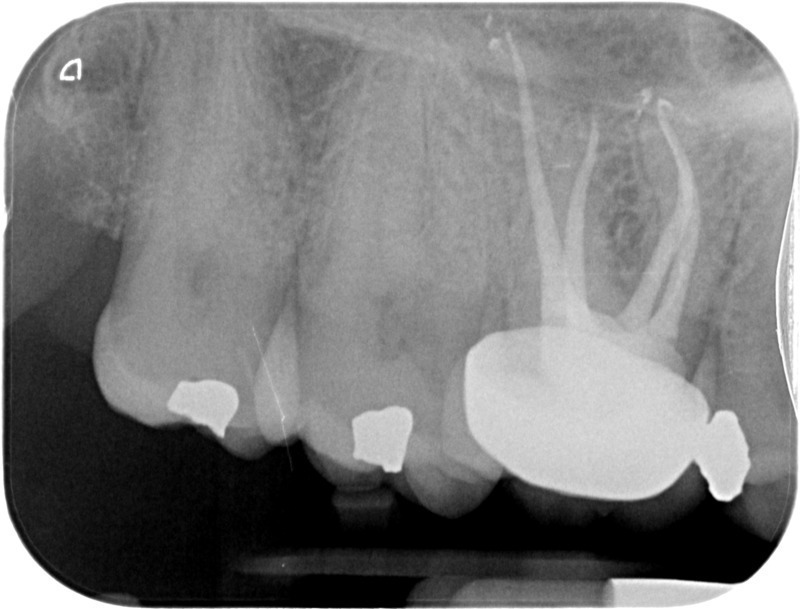

• Traitement endodontique : Sous anesthésie locale et à travers la protection d’un champ opératoire nous accédons à la pulpe de la dent à soigner, puis aux canaux de ses racines que nous devons désinfecter. Ce soin nécessite l’élimination complète de la source de contamination (souvent la carie) parfois sous une ancienne reconstitution ou une couronne qu’il faut alors retirer. Une fois le nettoyage et la mise en forme des canaux réalisés, nous les obturons de façon hermétique avec un ciment et un matériau thermoplastique appelé Gutta Percha. Ceci afin d’empêcher une nouvelle prolifération bactérienne et d’assurer le maintien de la dent dans ses structures de soutien (ligament parodontal et os alvéolaire). L’ouverture effectuée au centre de la dent sera d’abord refermée avec un pansement provisoire avant d’envisager ensemble la reconstitution d’usage : un composite, un inlay-onlay ou une couronne.

Avant